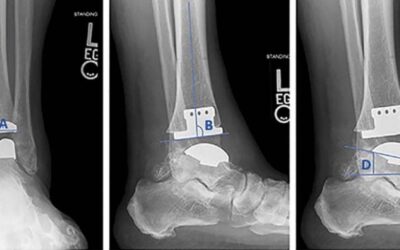

Salto Talaris Fixed-Bearing Total Ankle Arthroplasty: 10-Yr Results

In this longer-term follow-up of a limited cohort (48 patients/50 ankles, average age at index surgery: 64 years), Salto Talaris fixed-bearing total ankle arthroplasty demonstrated good long-term survival (Kaplan-Meier estimated survivorship was 84.2%) with relatively low rates of revision or other complications. Patient-reported outcome and range of motion measures revealed good stability.